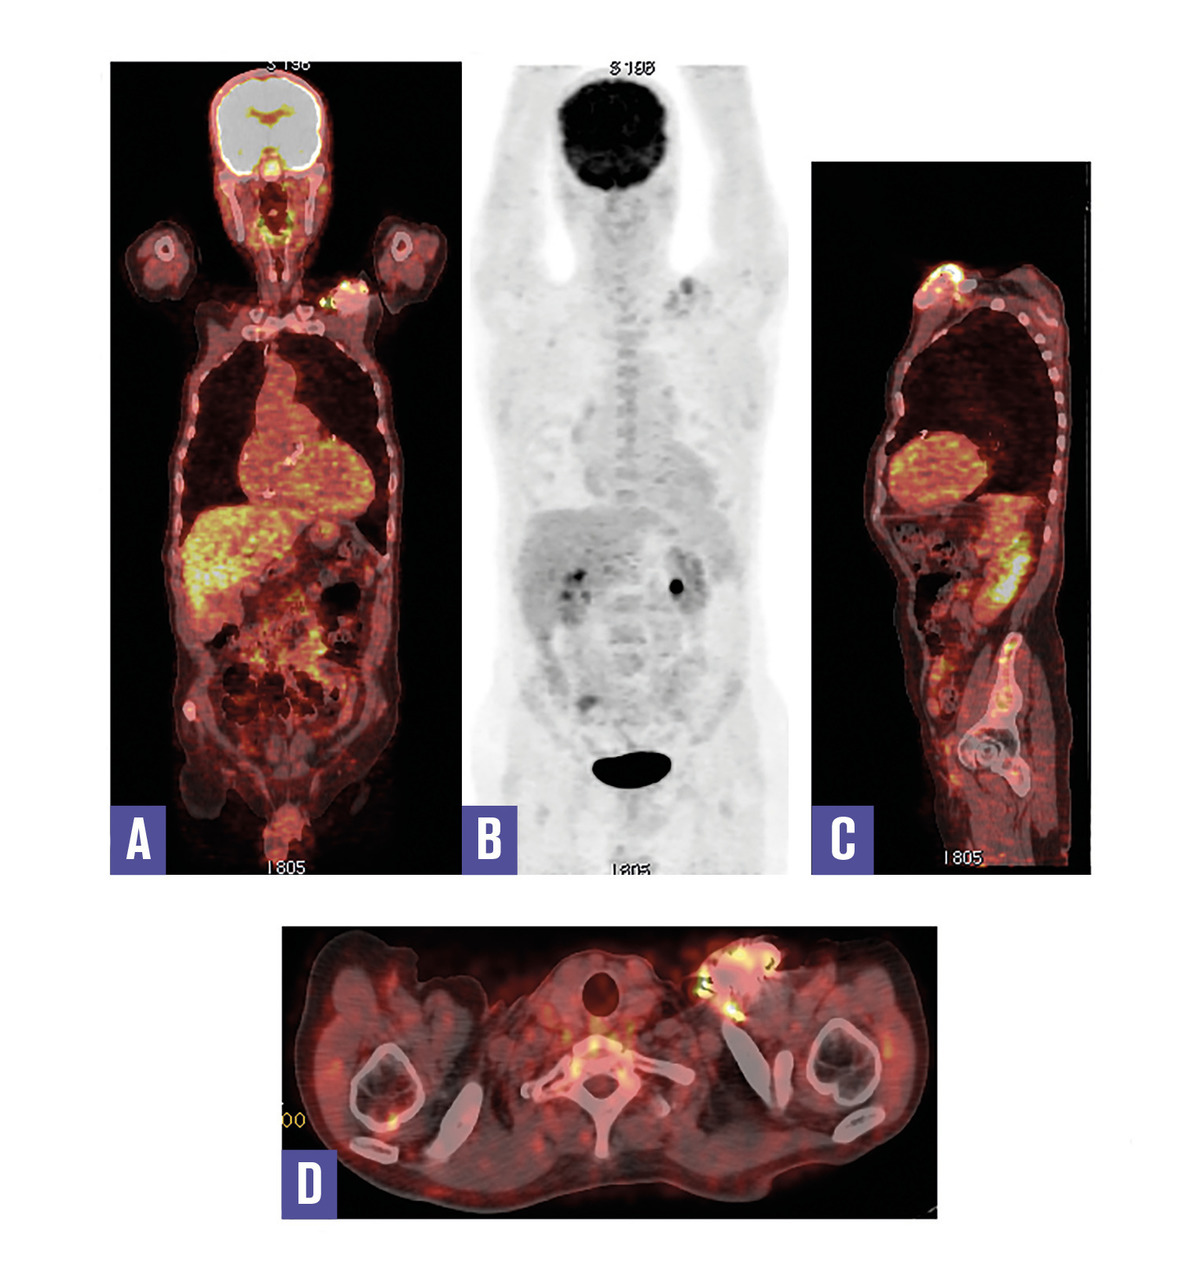

Cet homme de 71 ans, qui avait bénéficié d’un remplacement valvulaire aortique il y a 2 ans et de la pose d’un défibrillateur automatique implantable il y a 8 mois, consultait pour une fièvre prolongée. L’auscultation cardiaque notait un souffle au foyer aortique. La protéine C-réactive et la procalcitonine étaient élevées, les hémocultures étaient positives à Streptococcus aureus ; l’échographie transœsophagienne ne montrait pas de végétation sur la valve prothétique. Une tomographie par émission de positons couplée à la tomo- densitométrie au 18fluorodésoxyglucose (TEP-TDM au 18F-FDG) était réalisée, elle était négative au niveau cardiaque ; en revanche elle montrait un hypermétabolisme pathologique au pourtour du boîtier du défibrillateur implanté au niveau prépectoral gauche. Ce dernier était retiré et l’examen bactériologique confirmait la présence de Streptococcus aureus.

Le défibrillateur automatique implantable est un stimulateur cardiaque capable, en plus de la stimulation antibradycardique classique, d’identifier et de traiter les arythmies ventriculaires malignes.1 Son infection est une maladie sévère, à motricité élevée. Le nombre croissant de patients porteurs de dispositif électronique intracardiaque explique l’augmentation de survenue des endocardites infectieuses. À l’inverse de l’infection locale au niveau du boîtier, l’endocardite est une infection qui s’étend aux sondes et aux valves cardiaques. Cependant, la différenciation entre les deux est souvent difficile.2 La TEP-FDG pourrait s’avérer utile dans ces situations diagnostiques délicates qui constituent souvent un défi pour le clinicien.